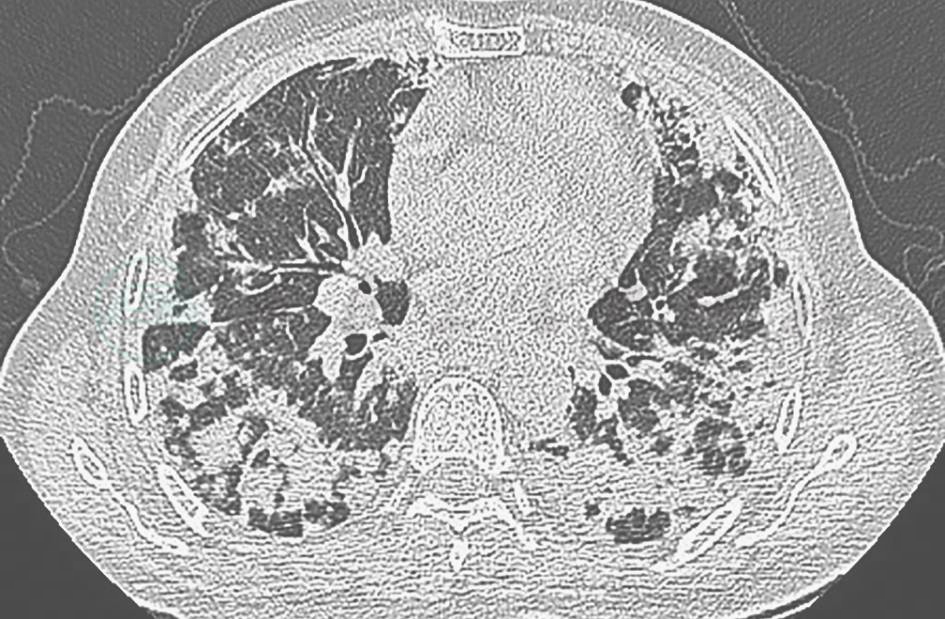

病毒性肺炎:严重急性呼吸道综合征(severe acute respiratory syndrome,SARS)、中东呼吸综合征(middle east respiratory syndrome,MERS)或H1N1等流感病毒(图1)所致的病毒性肺炎,常发病急骤,胸部影像学表现主要为间质性病变,可在数天内进展为“白肺”。腺病毒所致的病毒性肺炎可出现肺实变表现,该病多发生于儿童,但也有成年人发病的报道,除累及肺部以外,还可累及肝、肾、血液系统等,其病程有自限性。本例患者的临床表现与上述情况不符,可检测呼吸道病原协助鉴别。

图1 H1N1感染胸部影像学表现

胸部CT可见双肺多发小斑片磨玻璃实变影